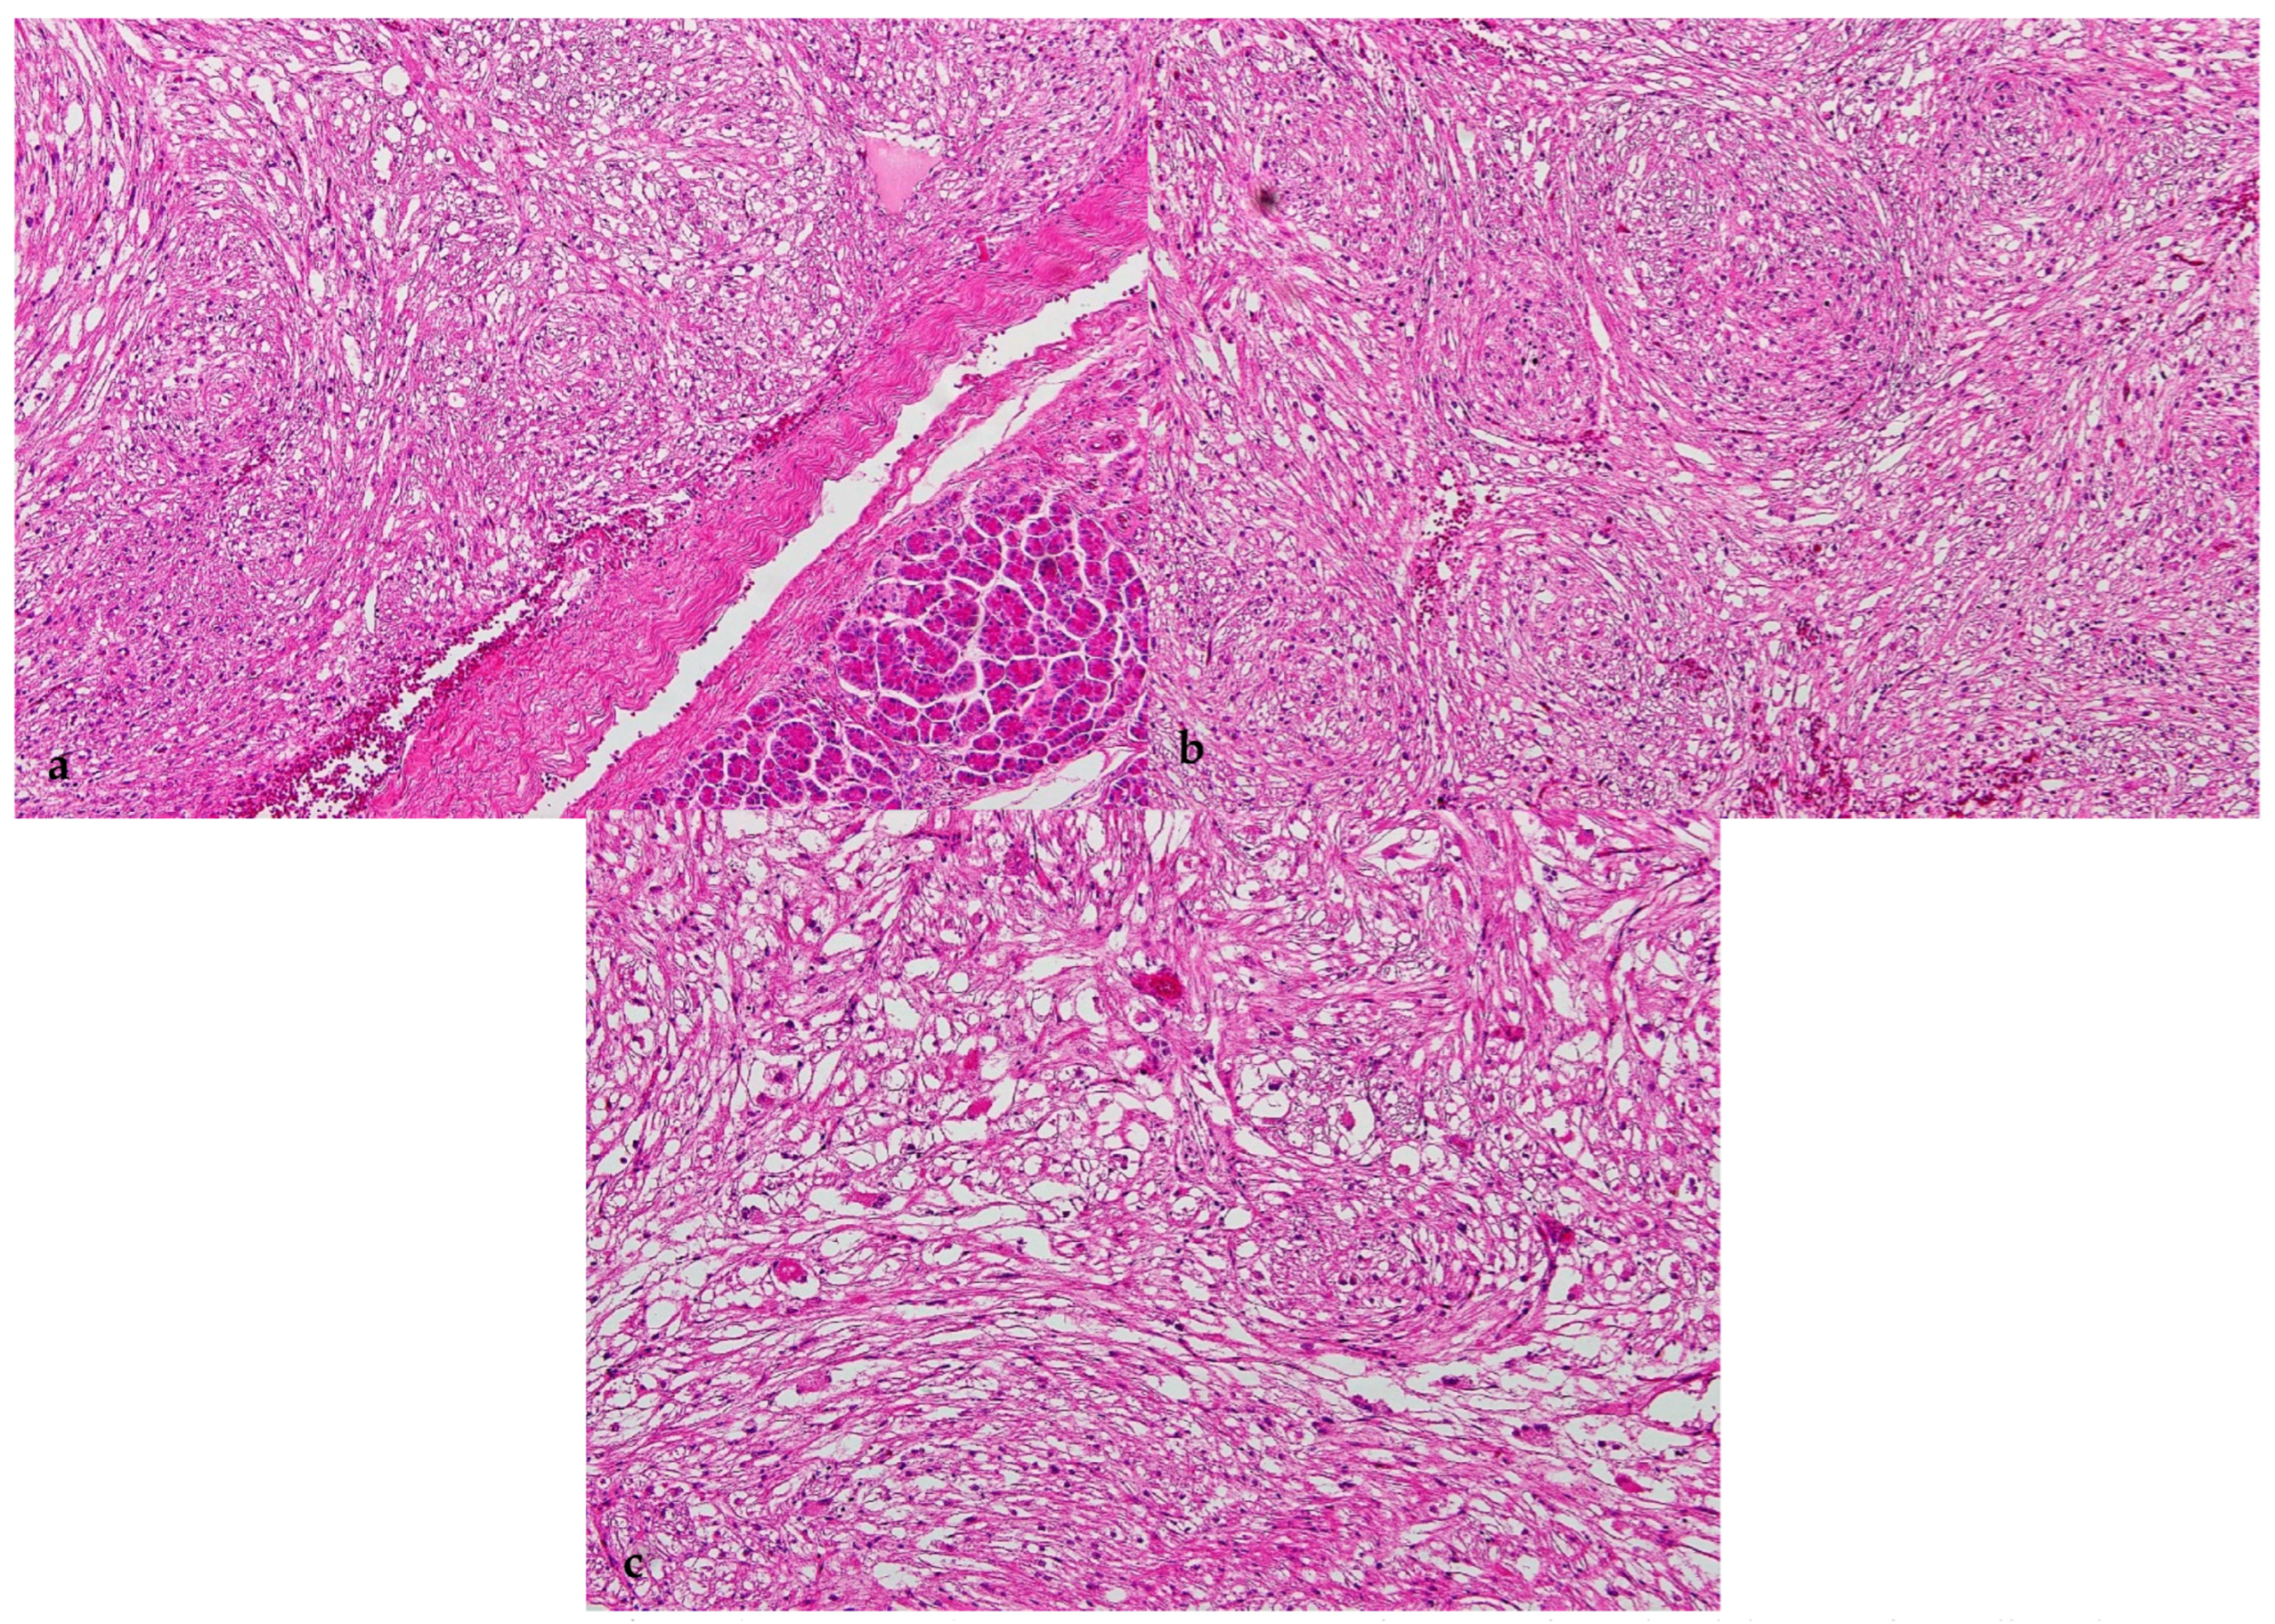

2. Case Report

2.2. Pathological Findings